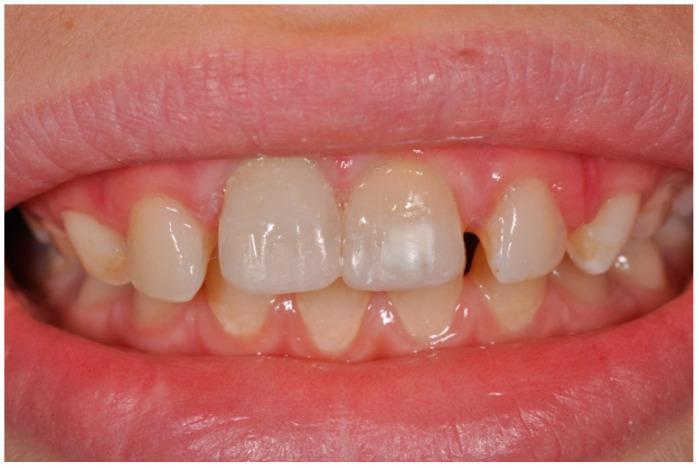

: Avulsion and reimplantation of permanent teeth represent a major challenge in terms of treatment and long-term prognosis. The present study reported clinical management of external root resorption of an avulsed and reimplanted maxillary central incisor. : A 9-year-old boy reported an uncomplicated crown fracture and avulsion of tooth 11 and complicated crown fracture of tooth 21 due to trauma. Reimplantation of element 11 was obtained within 30 min post-trauma and 3 days after both elements were diagnosed with necrotic pulp. In addition, tooth 11 showed early external root resorption. Both elements underwent endodontic treatment and root closure with apical plug using calcium-silicate-based cement. At 6-month follow-up root resorption appeared to be arrested. Twenty-four months after trauma the clinical results were stable, although signs and symptoms of ankylosis were observed. : An immediate endodontic approach and use of calcium-silicate-based cement seemed to contrast the progression of root resorption of an avulsed and reimplanted central incisor after 24 months of follow-up.

恒牙的脱位与再植在治疗及长期预后方面是一项重大挑战。本研究报告了一例上颌中切牙脱位再植后牙根外吸收的临床处理情况。:一名9岁男孩因外伤导致11号牙冠折未伴复杂情况及脱位,21号牙冠折伴复杂情况。外伤后30分钟内完成1号牙再植,两颗牙均被诊断为牙髓坏死3天后进行处理。此外,11号牙出现早期牙根外吸收。两颗牙均接受了根管治疗,并使用硅酸钙基水门汀进行根尖封闭以促进牙根闭合。6个月随访时,牙根吸收似乎停止。外伤24个月后临床结果稳定,尽管观察到了牙齿粘连的体征和症状。:经过24个月的随访,立即进行根管治疗并使用硅酸钙基水门汀似乎抑制了脱位再植中切牙牙根吸收的进展。